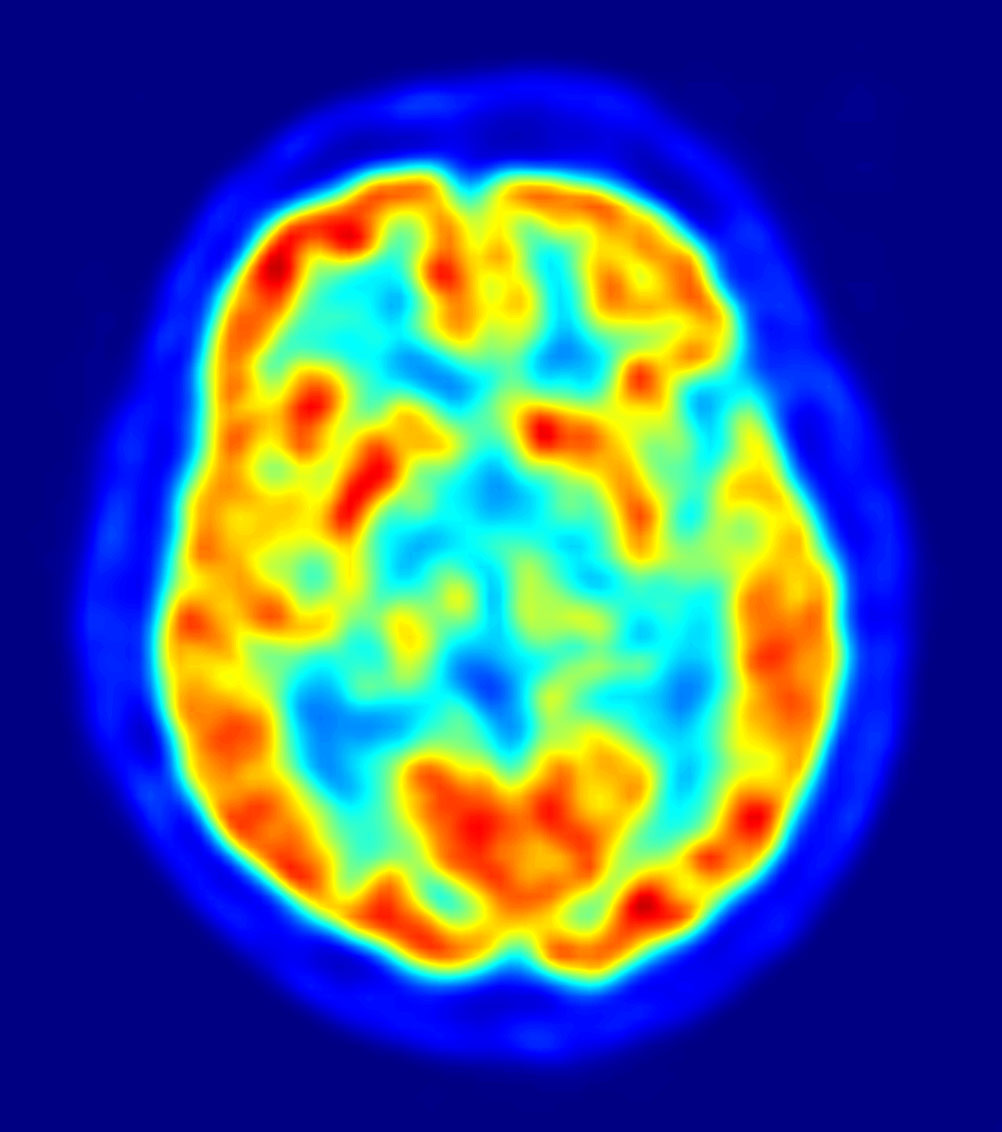

Dans la très réputée revue Nature Neuroscience, une équipe de chercheurs américains démontre qu’avec une IRM du cerveau et la bonne lecture, on peut à présent déterminer à quel point une personne peut être intelligente. Par intelligence, les scientifiques entendent être capable d’une capacité de raisonnement et d’abstraction élaborée.

Pour prouver cela, les chercheurs ont utilisé 126 sujets qu’ils ont branchés sur différentes machines, puis leur ont fait passer plusieurs tests concernant les capacités motrices, la mémoire, l’intelligence, y compris un modèle à compléter. Ils analysent ensuite les résultats en observant quelles zones du cerveau ont été le plus stimulées. Une connexion forte entre le lobe frontal et les lobes pariétaux produisent un score d’intelligence fluide particulièrement élevé. Les deux régions en question sont responsables des hautes fonctions neuronales.

De plus il apparaît qu’ont peut à présent, également, faire une sorte d’empreinte digitale des connexions neuronales de chacun, qui sont uniques à chaque individu. Donc grâce à un scanner, les scientifiques pourront nous dire si nous sommes fait pour tel ou tel poste, mais cela soulève pas mal de questions. Tout d’abord, cette étude laisse sous-entendre qu’il y aurait au moins deux catégories de personnes, celles qui sont intelligentes et et celles qui le sont moins. Ainsi, nonobstant nos efforts et notre acquis, ceux qui auraient été déterminés comme moins intelligents seraient forcément plus limités dans la vie.